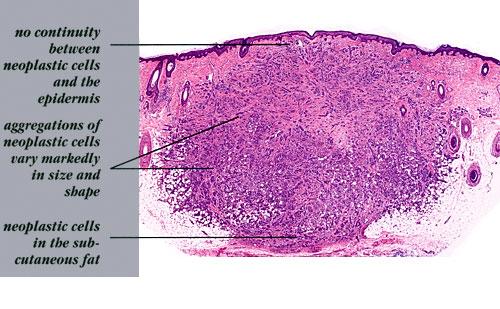

metastasis